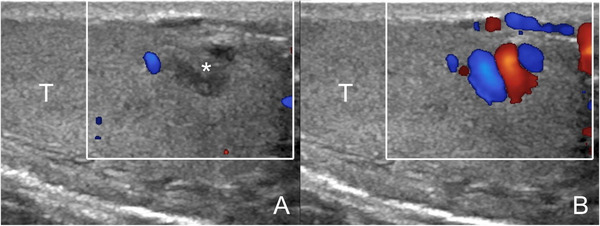

Intratesticular varicocoeles can resemble lesions when investigated in the supine position at rest, but reveal their vascular nature when the patient is investigated in standing position during Valsalva manoeuver (Figure 9). Venous reflux is identified, a feature that allows differentiation with other vascular intratesticular lesions, such haemangiomas and arteriovenous malformations, which show arterial flows and arterialized‐venous spectral waveform. 5

FIGURE 9.

Intratesticular varicocoele. Images obtained at rest (A) and during Valsalva's manoeuver (B). At rest (A) a hypoechoic lesion is seen (asterisk) resembling a tumor. During Valsalva (B) enlarged intratesticular veins with reflux are revealed (T = testis)